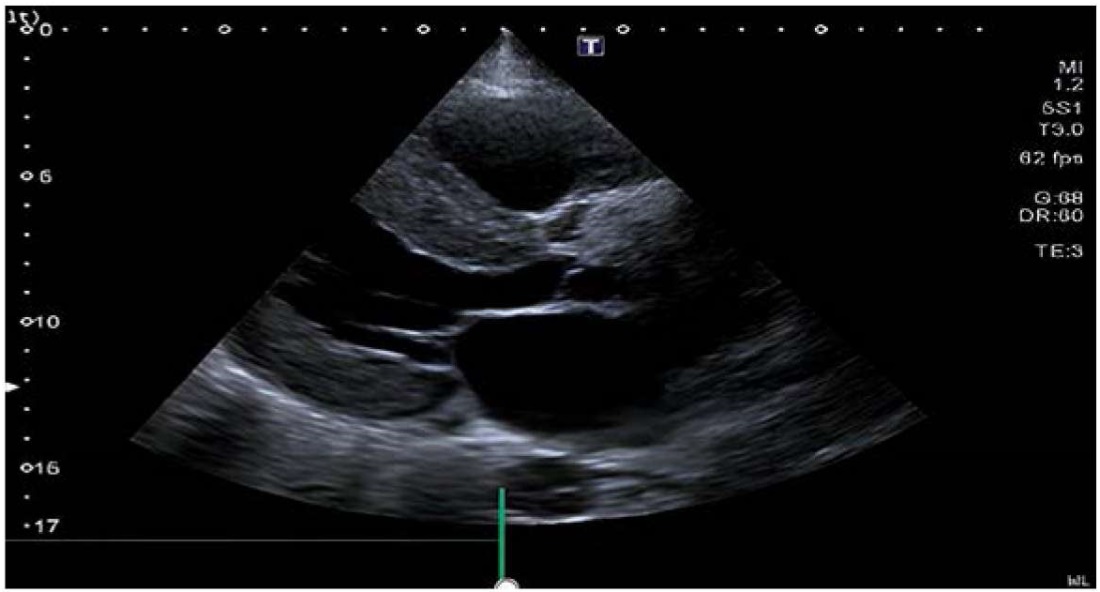

Повторно проведена ЭХО-КГ (аппарат Toshiba Aplio 500) (рис. 2). В сравнении c исследованием, выполненным за 6 месяцев до настоящего, наблюдалось увеличение выраженности гипертрофии ЛЖ, значительный рост показателей толщины МЖП и ЗСЛЖ, увеличение индекса массы миокарда ЛЖ, превышавшего двукратно нормативные показатели. При этом фракция выброса сохранена, зоны нарушения локальной сократимости достоверно не определялись (табл. 1).

Рисунок 2. Эхокардиография (апикальное четырёхкамерное сечение)

Figure 2. Echocardiography (apical four-chamber section)

При ультразвуковом исследовании сердца первым настораживающим признаком в отношении амилоидоза является концентрическое утолщение стенки ЛЖ, которое нередко превышает 15 мм, при этом толщина стенки более 18 мм встречается гораздо чаще при ATTR-форме, чем при AL-амилоидозе [17]. Важно отметить, что в отличие от истинной гипертрофии желудочков эхогенность миокарда при амилоидозе выше, его текстура имеет типичный «зернистый, сверкающий» вид [17][21]. Также может обнаруживаться двустороннее увеличение предсердий и утолщение межпредсердной перегородки [22]. Предсердия могут стать местом образования тромбов даже при отсутствии аритмии вследствие низкого ударного объёма и неровной поверхности эндокарда предсердий из-за инфильтрации амилоидом [17][22]. Иногда наблюдаются плевральный или перикардиальный выпоты [22], что и было обнаружено нами у больной, причём особенно привлекала внимание скорость прогрессии утолщения миокарда ЛЖ: за 6 месяцев толщина МЖП увеличилась на 6,2 мм, а ЗСЛЖ — на 5,5 мм. Но наиболее специфичным инструментальным признаком амилоидной кардиомиопатии считается нарушение продольной деформации базальных и средних сегментов ЛЖ с сохранением в апикальных сегментах, получивший название «вишенка на торте» (или «бычий глаз»), редко выявляющееся при других кардиомиопатиях [15][17]. К сожалению, технические возможности не позволили оценить данный признак у нашей пациентки.